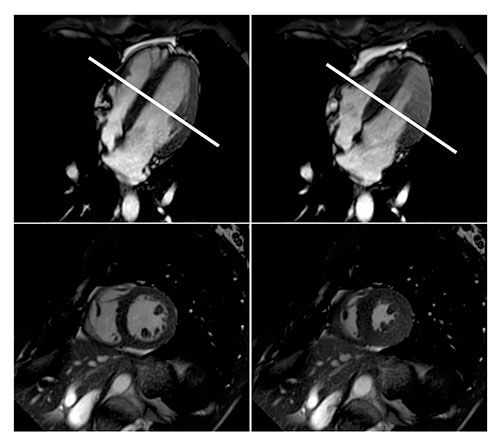

Cardiovascular MR-guided care may reduce the number of unnecessary angiograms performed on patients with angina pectoris.

Predictive ability for major adverse cardiac events of cardiovascular MRI for patients compared with SPECT.